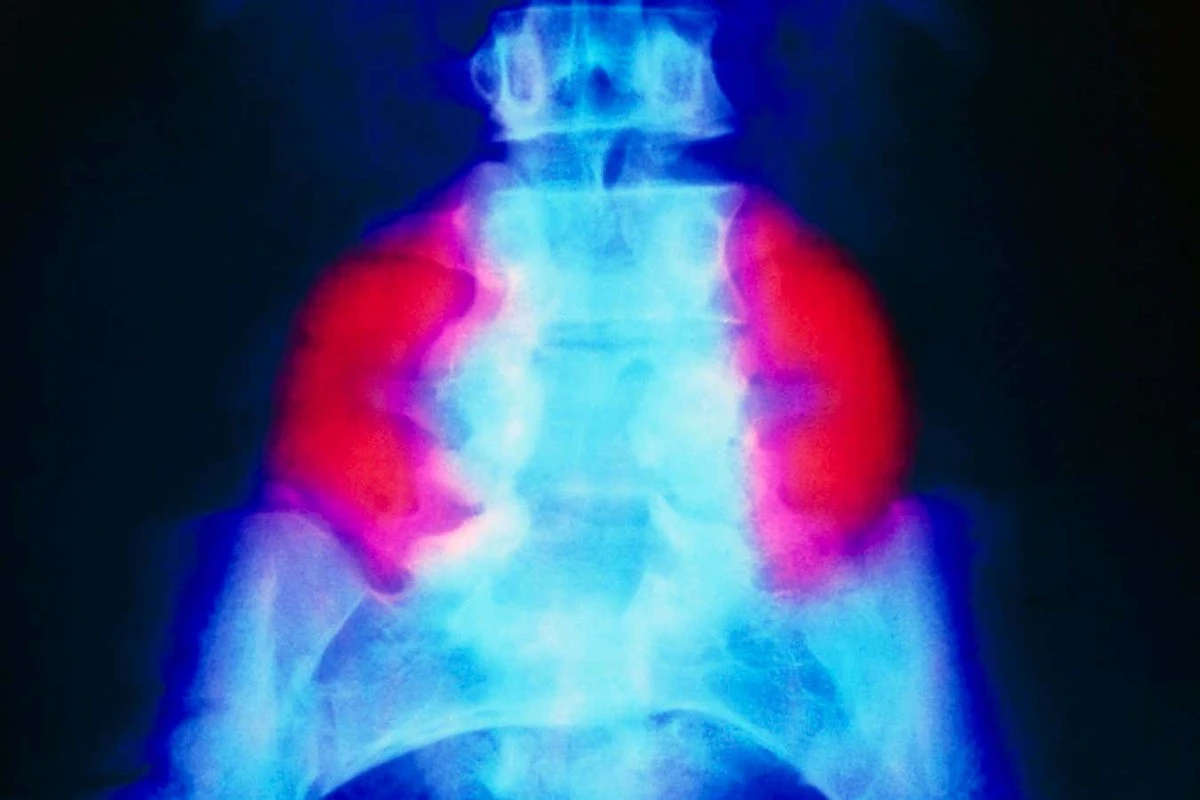

In Nederland en de rest van de wereld is een operatie in de baarmoeder al langer mogelijk. Chirurgen hechten de rug van de foetus dicht om verdere schade te voorkomen. Maar er is een nuance: hoewel de rug dicht is, herstelt het beschadigde zenuwweefsel zich vaak niet.

Onderzoekers van UC Davis hebben iets unieks gedaan. Ze gebruikten stamcellen uit donor-placentas en verwerkten deze in een speciale, plakkerige matrix van eiwitten. Tijdens de operatie in de baarmoeder wordt deze pleister direct op het open ruggetje geplaatst.

Het werkt eigenlijk als een biologische katalysator. De cellen scheiden stoffen af die het ruggenmerg helpen herstellen terwijl de baby nog groeit. Bij de eerste baby's die deze behandeling kregen, zagen artsen op MRI-scans dat hersencomplicaties volledig verdwenen.